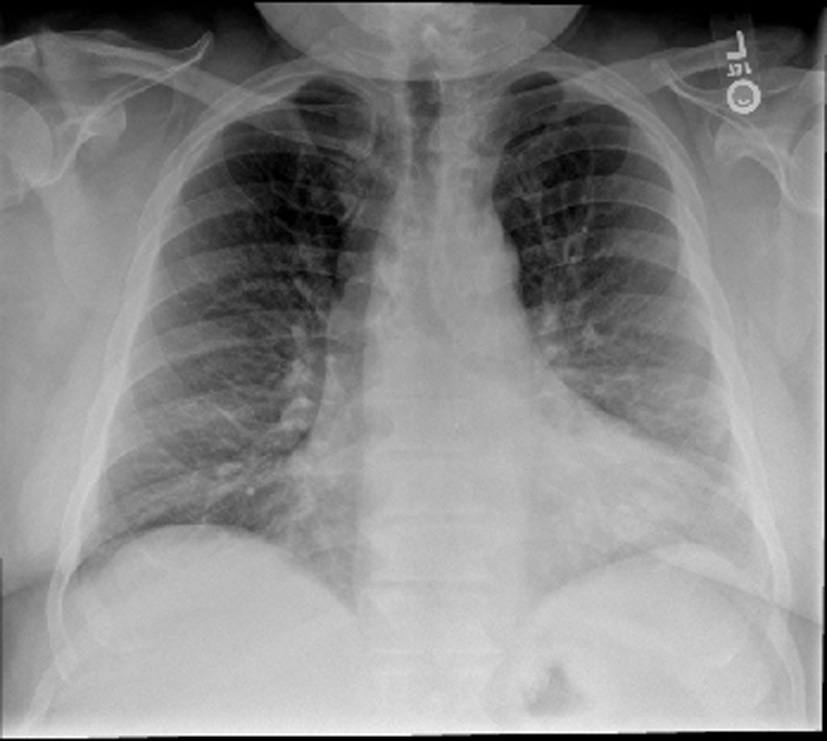

His vital signs were stable with a blood pressure of 144/70, heart rate of 64 and oxygen saturation of 94% on room air. On physical examination, he was a morbidly obese gentleman with marked edema in his upper and lower extremities as well as his neck and face. Lungs were clear and heart sounds were distant but unremarkable. Abdomen was soft and non-distended. Basic metabolic panel, complete blood count, total protein, albumin, liver function tests, cardiac enzymes and thyroid stimulating hormone were all within normal limits. Brain natriuretic peptide was 20 pg/mL. ECG showed a normal sinus rhythm with a right bundle branch block unchanged from prior as well as no dynamic ST changes. An echocardiogram was poor quality due to body habitus, but had grossly normal ventricular function. Chest X-ray (Fig. 1) and CT chest (Fig. 2) showed no evidence of pulmonary edema, pneumonia, or pulmonary embolism. Venous duplex ruled out acute venous thrombosis.

![]() Click for large image | Figure 1. Chest X-ray. The lungs are clear without focal consolidation, pleural effusion, or pneumothorax. Normal pulmonary vasculature. Apparent enlargement of the cardiac silhouette is seen to be secondary to prominent pericardiac fat, as identified on the recent CT. |